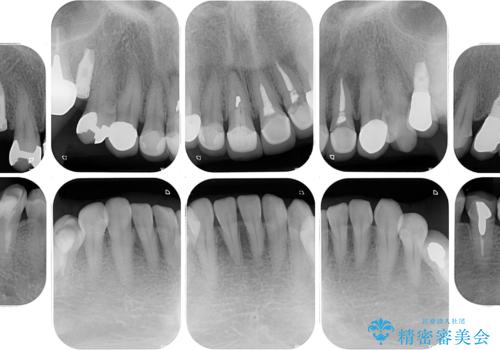

右下のむし歯が歯肉縁下に及んでおり、歯周外科処置(歯冠長延長術)を行った上で、根管治療を行い、状態を整えて補綴治療を行うこととしました。

上顎前歯の根尖病変に痛みがありましたが、既に前歯が補綴治療済みであっため、外科的歯内療法(歯根端切除術)を行うことで解決することとしました。